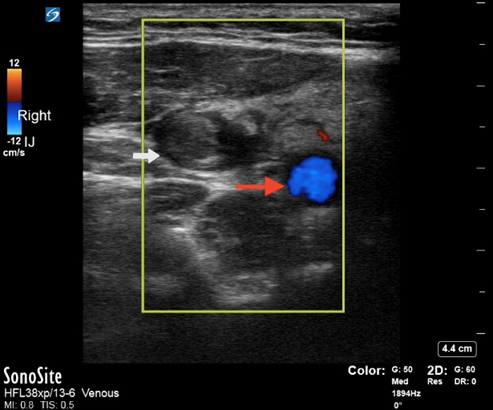

Imaging modalities include CT scanning of the neck and chest with IV contrast.29 Ultrasound of the neck and internal jugular may be considered as well, although that is less sensitive than CT and does not help to differentiate potential complications, such as septic pulmonary emboli. Benefits of ultrasound are the rapidity in which it may be performed at the bedside and the ability to perform the study on unstable patients at the bedside. Ultrasound of the internal jugular vein may demonstrate thrombus within the vein. (See Figure 6.) Additionally, bedside point-of-care ultrasound also enables the ability to perform a bedside cardiac evaluation for potential right heart strain in the setting of septic pulmonary emboli and potentially allows for the diagnosis of right-sided endocarditis, which can mimic Lemierre’s syndrome.

Figure 6. Ultrasound of a Thrombus in the Internal Jugular |

Point-of-care ultrasound with Doppler demonstrating a thrombus in the internal jugular vein (white arrow) and carotid artery (red arrow). Courtesy of Daniel Migliaccio, MD. |